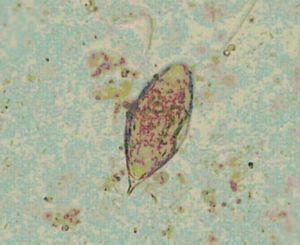

Caso 2. Varón de 12 años, nacido en Gambia que llegó a España hace 2 meses. Acude por primera vez a nuestra consulta por un problema dermatológico. En la anamnesis su madre refiere que a veces la orina contiene sangre. No se acompaña de molestias al orinar. En su país acudía con frecuencia a bañarse a un río. En el examen físico destaca: lesión compatible con tinea capitis. En las exploraciones complementarias el sedimento de orina hematíes es de 18-30/c y el cultivo negativo. En el examen parasitológico de orina se observan huevos de S. haematobium (fig. 1). Hemograma: Hb 10,5 g/dl; hematócrito: 32,2 %; leucocitos: 8,00 mill/μl; eosinófilos, 9.00 %. La bioquímica, las serologías y gota gruesa son normales. Las ecografías renal y vesical son normales. Se trata con 40 mg/kg de praziquantel en dosis única. El control de orina a los 3 meses es normal. En los 12 meses de seguimiento no se ha repetido la hematuria.

Figura 1. Examen en fresco de orina del caso 2. Se observan huevos de Schistosomas haematobium con espícula terminal.